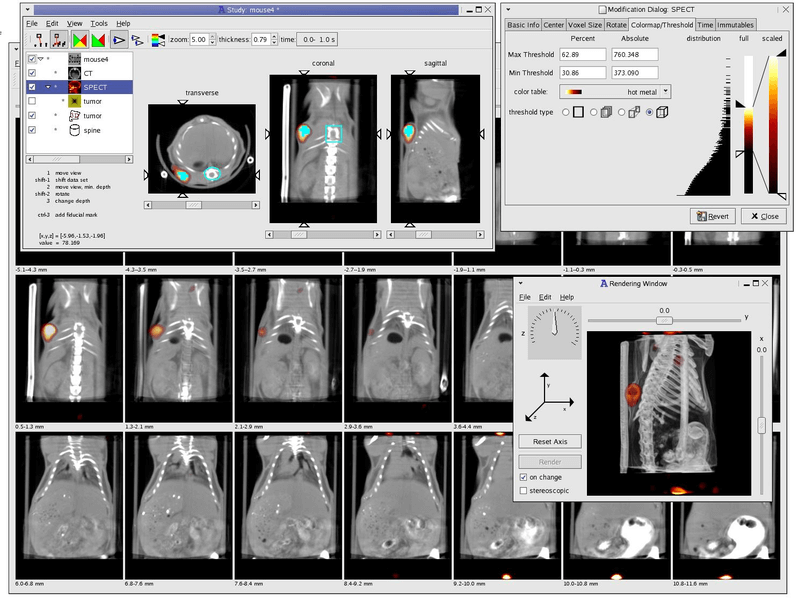

1. Amide

Amide is a cross-platform GTK+ tool for viewing, registering, and analyzing volumetric medical imaging data sets.

It uses a GUI with a long feature list including loading multiple data sets at once, generating fly through movies as MPEG1 files, an anisotropic filtering wizard, thresholding datasets independently and in bulk, etc.